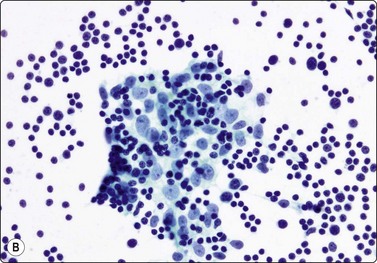

Fig. 9.1 Thymoma, lymphoepithelial

(A) Cohesive fragments of tumor tissue in a background of lymphoid cells (Pap, LP); (B) Cohesive cluster. Epithelial cells visible centrally Pap HP; (C) Cell block, indistinct epithelial cells (H&E, HP); (D) Cell block, reticular pattern of epithelial cell staining for AE1+3 keratins (IPOX, LP).

Tissue section; biphasic cell population (H&E, HP).

The histologic classification of thymomas is complex, evolving, and still somewhat controversial. Such subclassification may prove challenging for the histopathologist and this is exaggerated with aspiration cytology. Clearly, there is a wide spectrum in the cytomorphology of thymomas. First, there is a broad range of appearances of benign thymoma cells among and even within some of these neoplasms; this is complicated by the varying proportions of lymphocyes present.

In the benign thymomas, the epithelial cells are usually cohesive (Figs 9.1, 9.5) but may also manifest a reduction in intercellular cohesion (Fig. 9.2). Epithelial cells are not immediately evident in the mixed tumors at low power but are discernible using the higher magnification.18,29,30 The epithelial cells are polygonal, oval, or spindle shaped with uniform to slightly irregular nuclear outlines possibly with cleaved or folded nuclei. Their nuclear chromatin is homogeneous, finely distributed and pale and, occasionally, small nucleoli are seen. Cell borders are indistinct, but nuclei are separated by moderate amounts of pale cytoplasm (Figs 9.2, 9.5). In one personally examined case of thymoma metastatic to lung, Hassall’s corpuscles were evident in the clumps of tumor cells (Fig. 9.4); this is a most unusual manifestation and will not be present in most thymomas. When there is a lymphoid population, the bimodal pattern enables one to make a virtually certain diagnosis.18,29,30 In pure epithelial or spindle cell forms, definitive diagnosis is more difficult, although in Dahlgren’s series29 most thymomas were diagnosed and in Tao’s 37 cases30 all FNAC diagnoses of thymoma were verified histologically. Ali and Erozan34 were able to diagnose all of their 14 cases using a combination of cytology, immunocytochemistry and clinical information, and Shin and Katz showed a high accuracy in a range of mediastinal lesions including 14 thymomas.35 Tao and others describe more variation in the degree of cohesion than we have seen, particularly in pure epithelial/nonspindle cell types.30 Overall, the most challenging and the most common in our experience are the lymphocyte-rich (type B1) thymomas, as the tumor cells may be obscured by the lymphocytes.